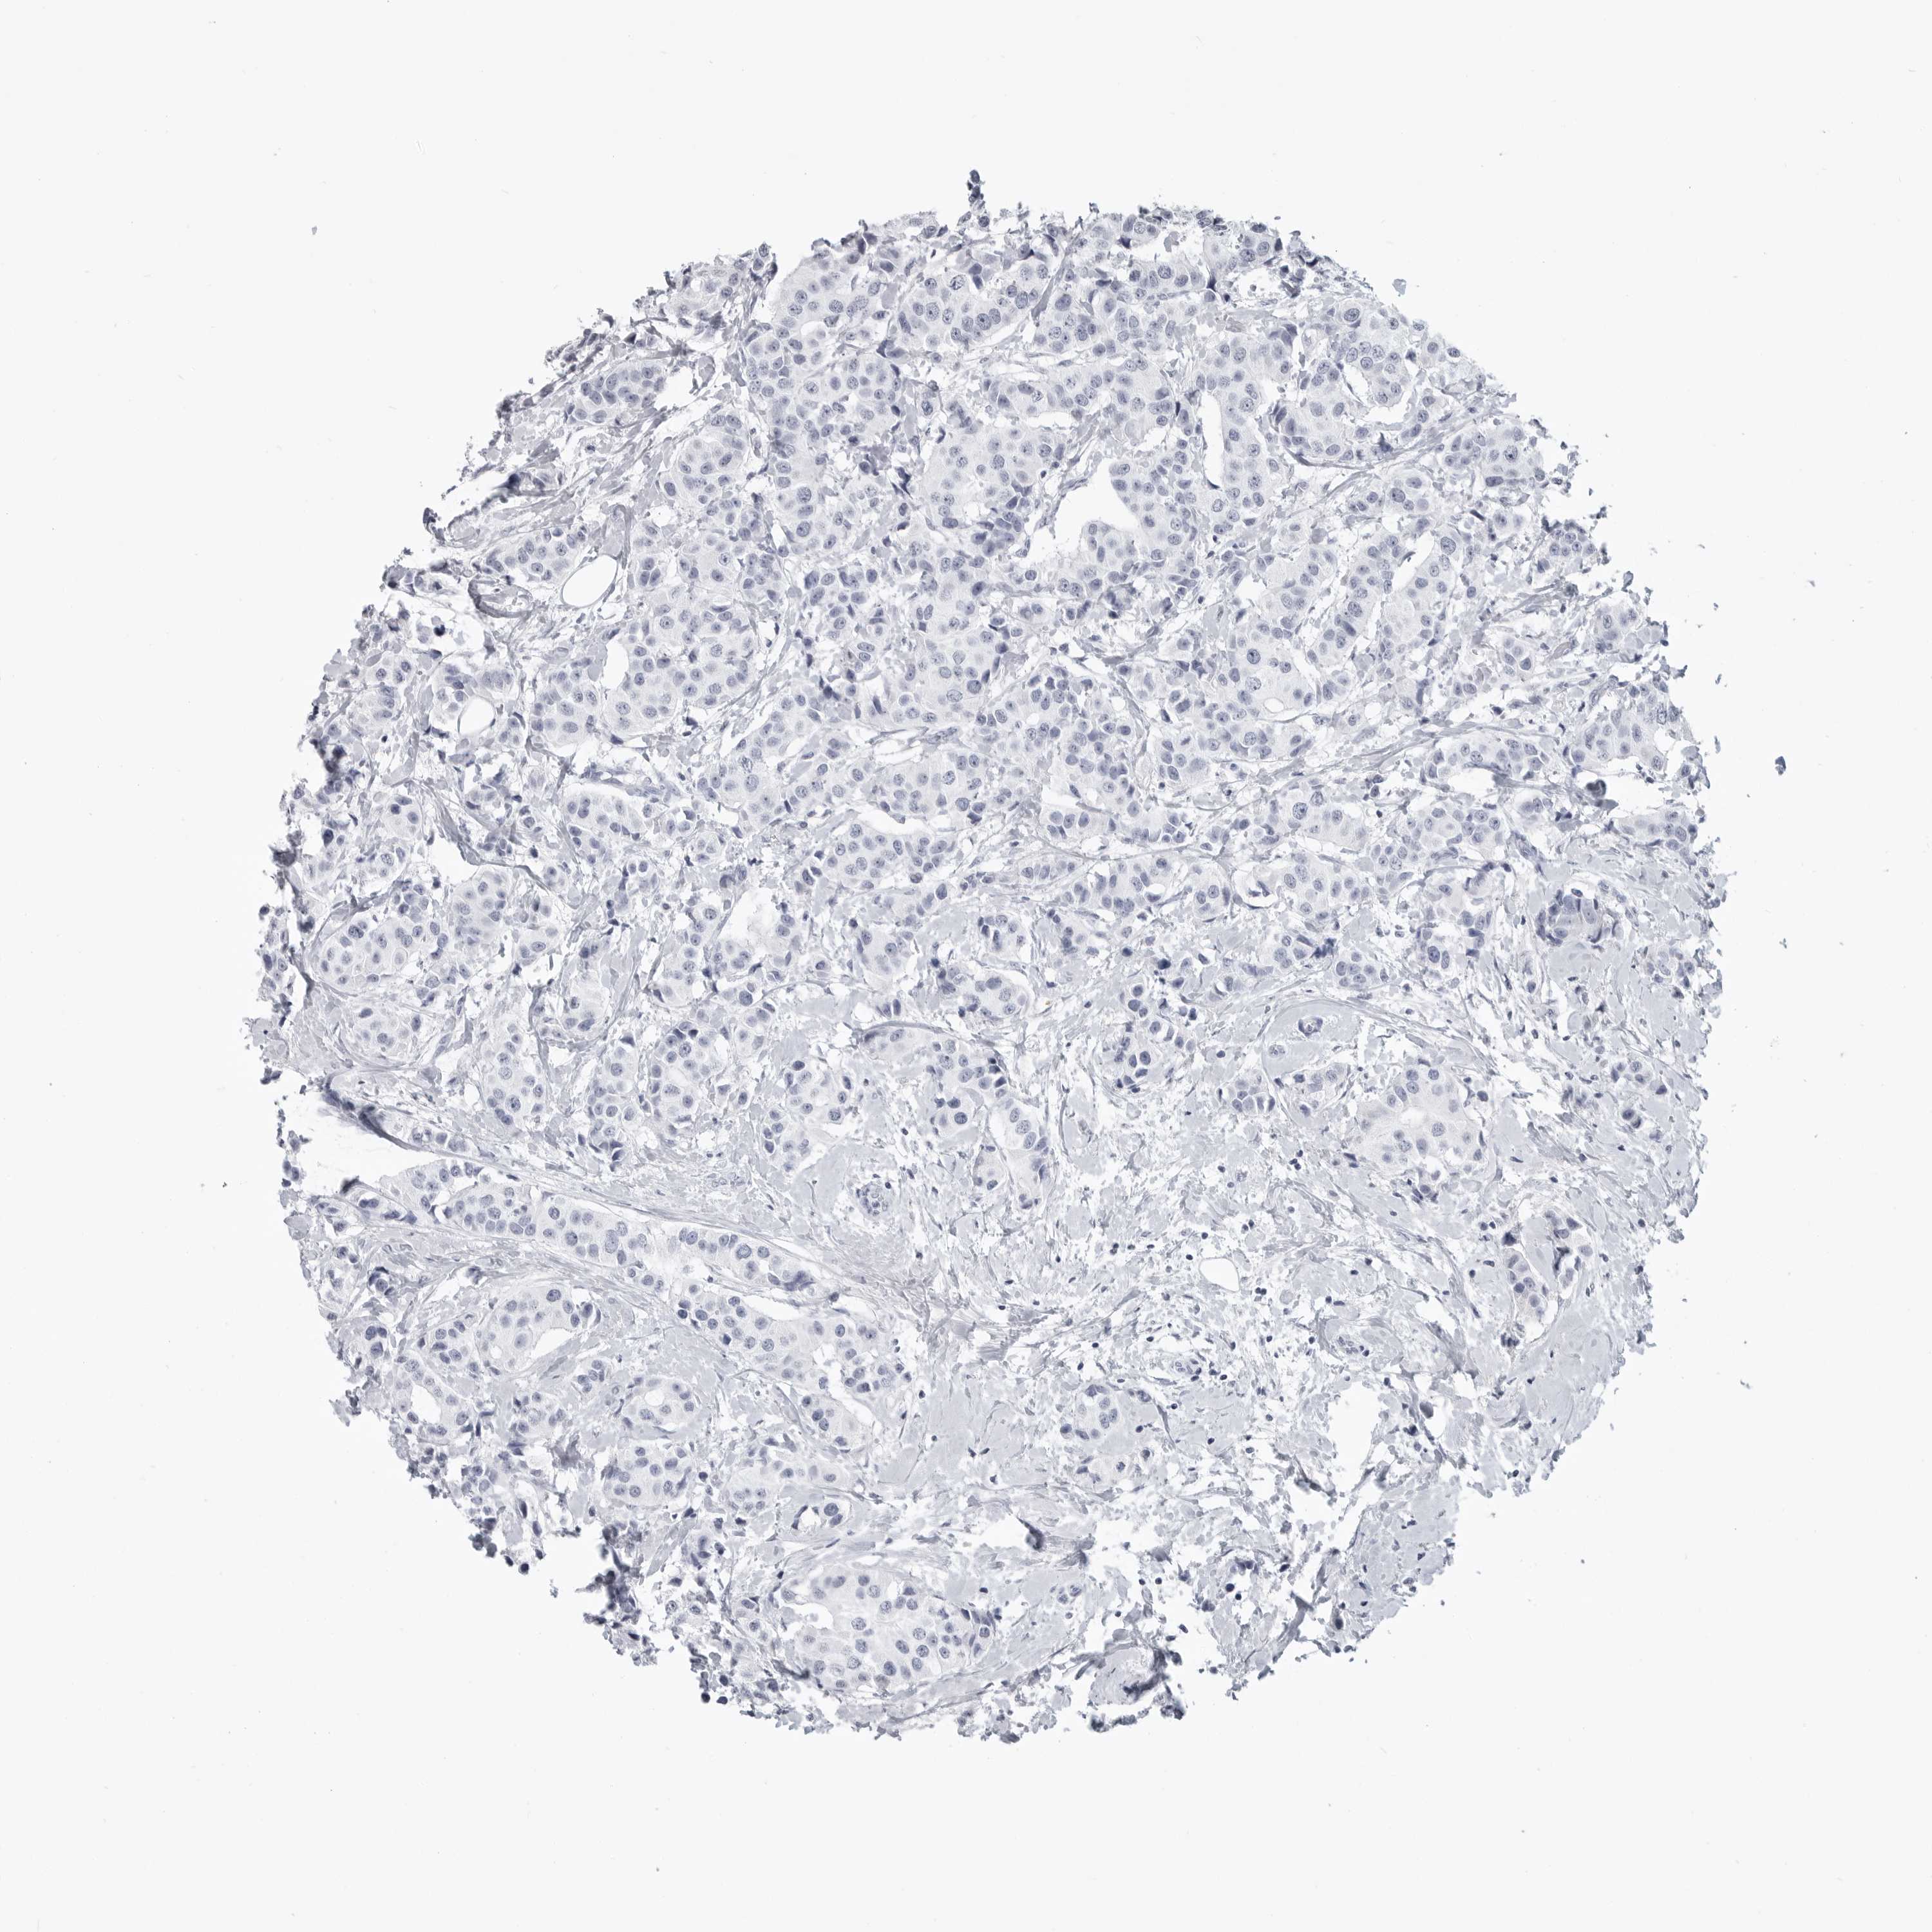

BRCA TCGA BRCA VALIDATION PROTEIN EXPRESSION

Breast cancer

Human cancer